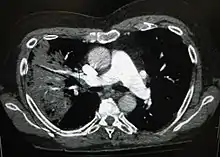

| 肺炎患者的胸腔X光照片,圈起處可看見明顯白色楔狀實變,此為細菌性肺炎的特色。(A chest X-ray showing a very prominent wedge-shape area of airspace consolidation in the right lung characteristic of bacterial pneumonia.) | |

由X光片來看,肺炎可以分類為大葉性肺炎、支氣管肺炎(有時也會稱為小葉性肺炎)及間質性肺病。細菌感染的社區性肺炎典型症狀有一個肺葉節段的肺實變,稱為大葉性肺炎[34][56]。然而並非所有的細菌性肺炎皆為大葉性肺炎,也並非所有的大葉性肺炎皆由細菌所引起,其他肺炎也會有類似的情形[34]。吸入性肺炎的特點是肺兩側底部及右肺葉呈現混濁[34]。病毒性肺炎的X光片可能是正常的,也可能有過度充氣、兩側大片浸潤、或是類似細菌性肺炎的肺實變情形[34]。肺炎在早期時可能無法從X光片上看出來,特別是在脫水的情況下,若有肥胖症其他肺部病史,也不易判斷[25]。有些情形,X射线计算机断层成像可以看出一些進一步的資訊[34]。